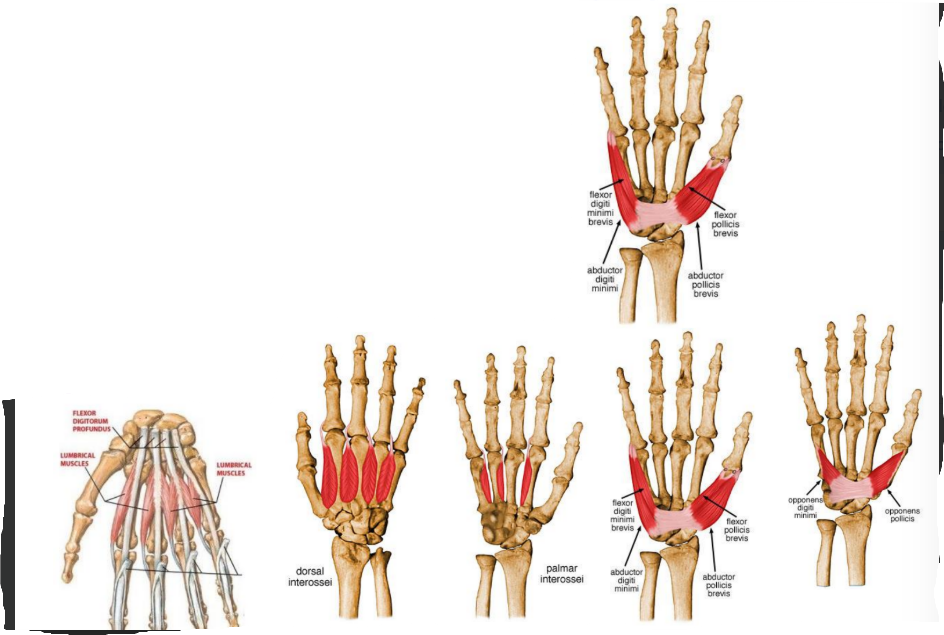

Intrinsic muscles of hand

Four thenar muscles

Abductor pollicis brevis

Flexor pollicis brevis

Opponens pollicis brevis

Adductor pollicis brevis

Four hypothenar muscles

Palmaris brevis

Abductor digiti minimi

Flexor digiti minimi

Oppenens digiti minimi

Four lumbricals

Three palmar interossei

Four dorsal interossei

Thenar muscles

ORIGIN | INSERTION | ACTION | INNERVATION | |

Abductor pollicis brevis | Flexor retinaculum and tubercle of scaphoid and crest of trapezium | Lateral of base of proximal phalanx of thumb | Abducts the thumb at metacarpophalangeal and carpometacarpal joint | Median nerve |

Flexor pollicis brevis | Superficial head- flexor retinaculum and crest of trapezium Deep- trapezoid and capitate bone | Lateral side of base of proximal phalanx | Flexes thumb | Median nerve |

Opponens pollicis | Flexor retinaculum and crest of trapezium | Lateral side of 1st metacarpal | Draws 1st metacarpal to oppose thumb | Median nerve |

Adductor pollicis | Oblique- base of 2nd and 4rd metacarpals, capitate and adjacent carpals Transverse- palmar surface of 3rd metacarpal | Medial side of base of proximal phalanx of thumb | Muscle adducts thumb from flexed or abducted position | Deep branch of ulnar nerve |

Hypothenar muscles

ORIGIN | INSERTION | ACTION | INNERVATION | |

Abductor digiti minimi | Pisiform bone | Medial side of base of proximal phalanx of little finger | Abducts little finger | Deep branch of ulnar nerve |

Flexor digiti minimi | Hook of hamate a/nd flexor retinaculum | Medial side of base of proximal phalanx of little finger | Flexes little finger at metacarpophalangeal joint | Deep branch of ulnar nerve |

Opponens digiti minimi | Hook of hamate and flexor retinaculum | Medial border of shaft of 5th metacarpal | Draws 5th metacarpal anteriorly and rotates it laterally, opposes thumb | Deep branch of ulnar nerve |

Palmaris brevis | Flexor retinaculum and palmar aponeurosis | Skin along medial border of hand | Helps with gripping | Superficial branch of ulnar nerve |

Interossei, palmar and lumbricals

ORIGIN | INSERTION | ACTION | INNERVATION | |

Dorsal interossei (4) | Adjacent sides of two metacarpals | Extensor expansions and base of proximal phalanges of digit 2-4 | Abduct digits from axial line Act with lumbricals to flex metacarpophalangeal joint and extend interphalangeal joint | Deep branch of ulnar nerve |

Palmar interossei | Palmar surfaces of 2nd, 4th and 5th metacarpals | Extensor expansions of digit and bases of proximal phalanges | Adduct digits towards axial line Assist lumbricals in flexing metacarpophalangeal joints and extending interphalangeal joints | Deep branch of ulnar nerve |

Lumbrical muscles | From tendon of flexor digitorum profundus | Dorsal digital expansion | Flex the metacarpophalangeal joints and extend the interphalangeal joints | 1st and 2nd lumbricals by median nerve 3rd and 4th lumbricals by deep branch of ulnar nerve |